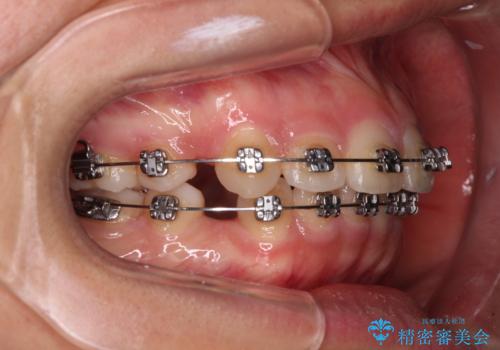

- メタルブラケット

上下ともに歯列が前方に突出していたため、上下左右の第一小臼歯4本を抜去する方針(既に上顎は抜歯されています)で、ワイヤー装置による矯正治療を行うこととしました。

舌の突出癖による影響もあったため、舌のトレーニングを並行して実施しました。

舌の突出癖があり、咬合力も強かったため、治療期間は長くなることが懸念されましたが、舌のトレーニングをしっかりと行っていただいたこともあり、2年弱で治療を終えることができました。